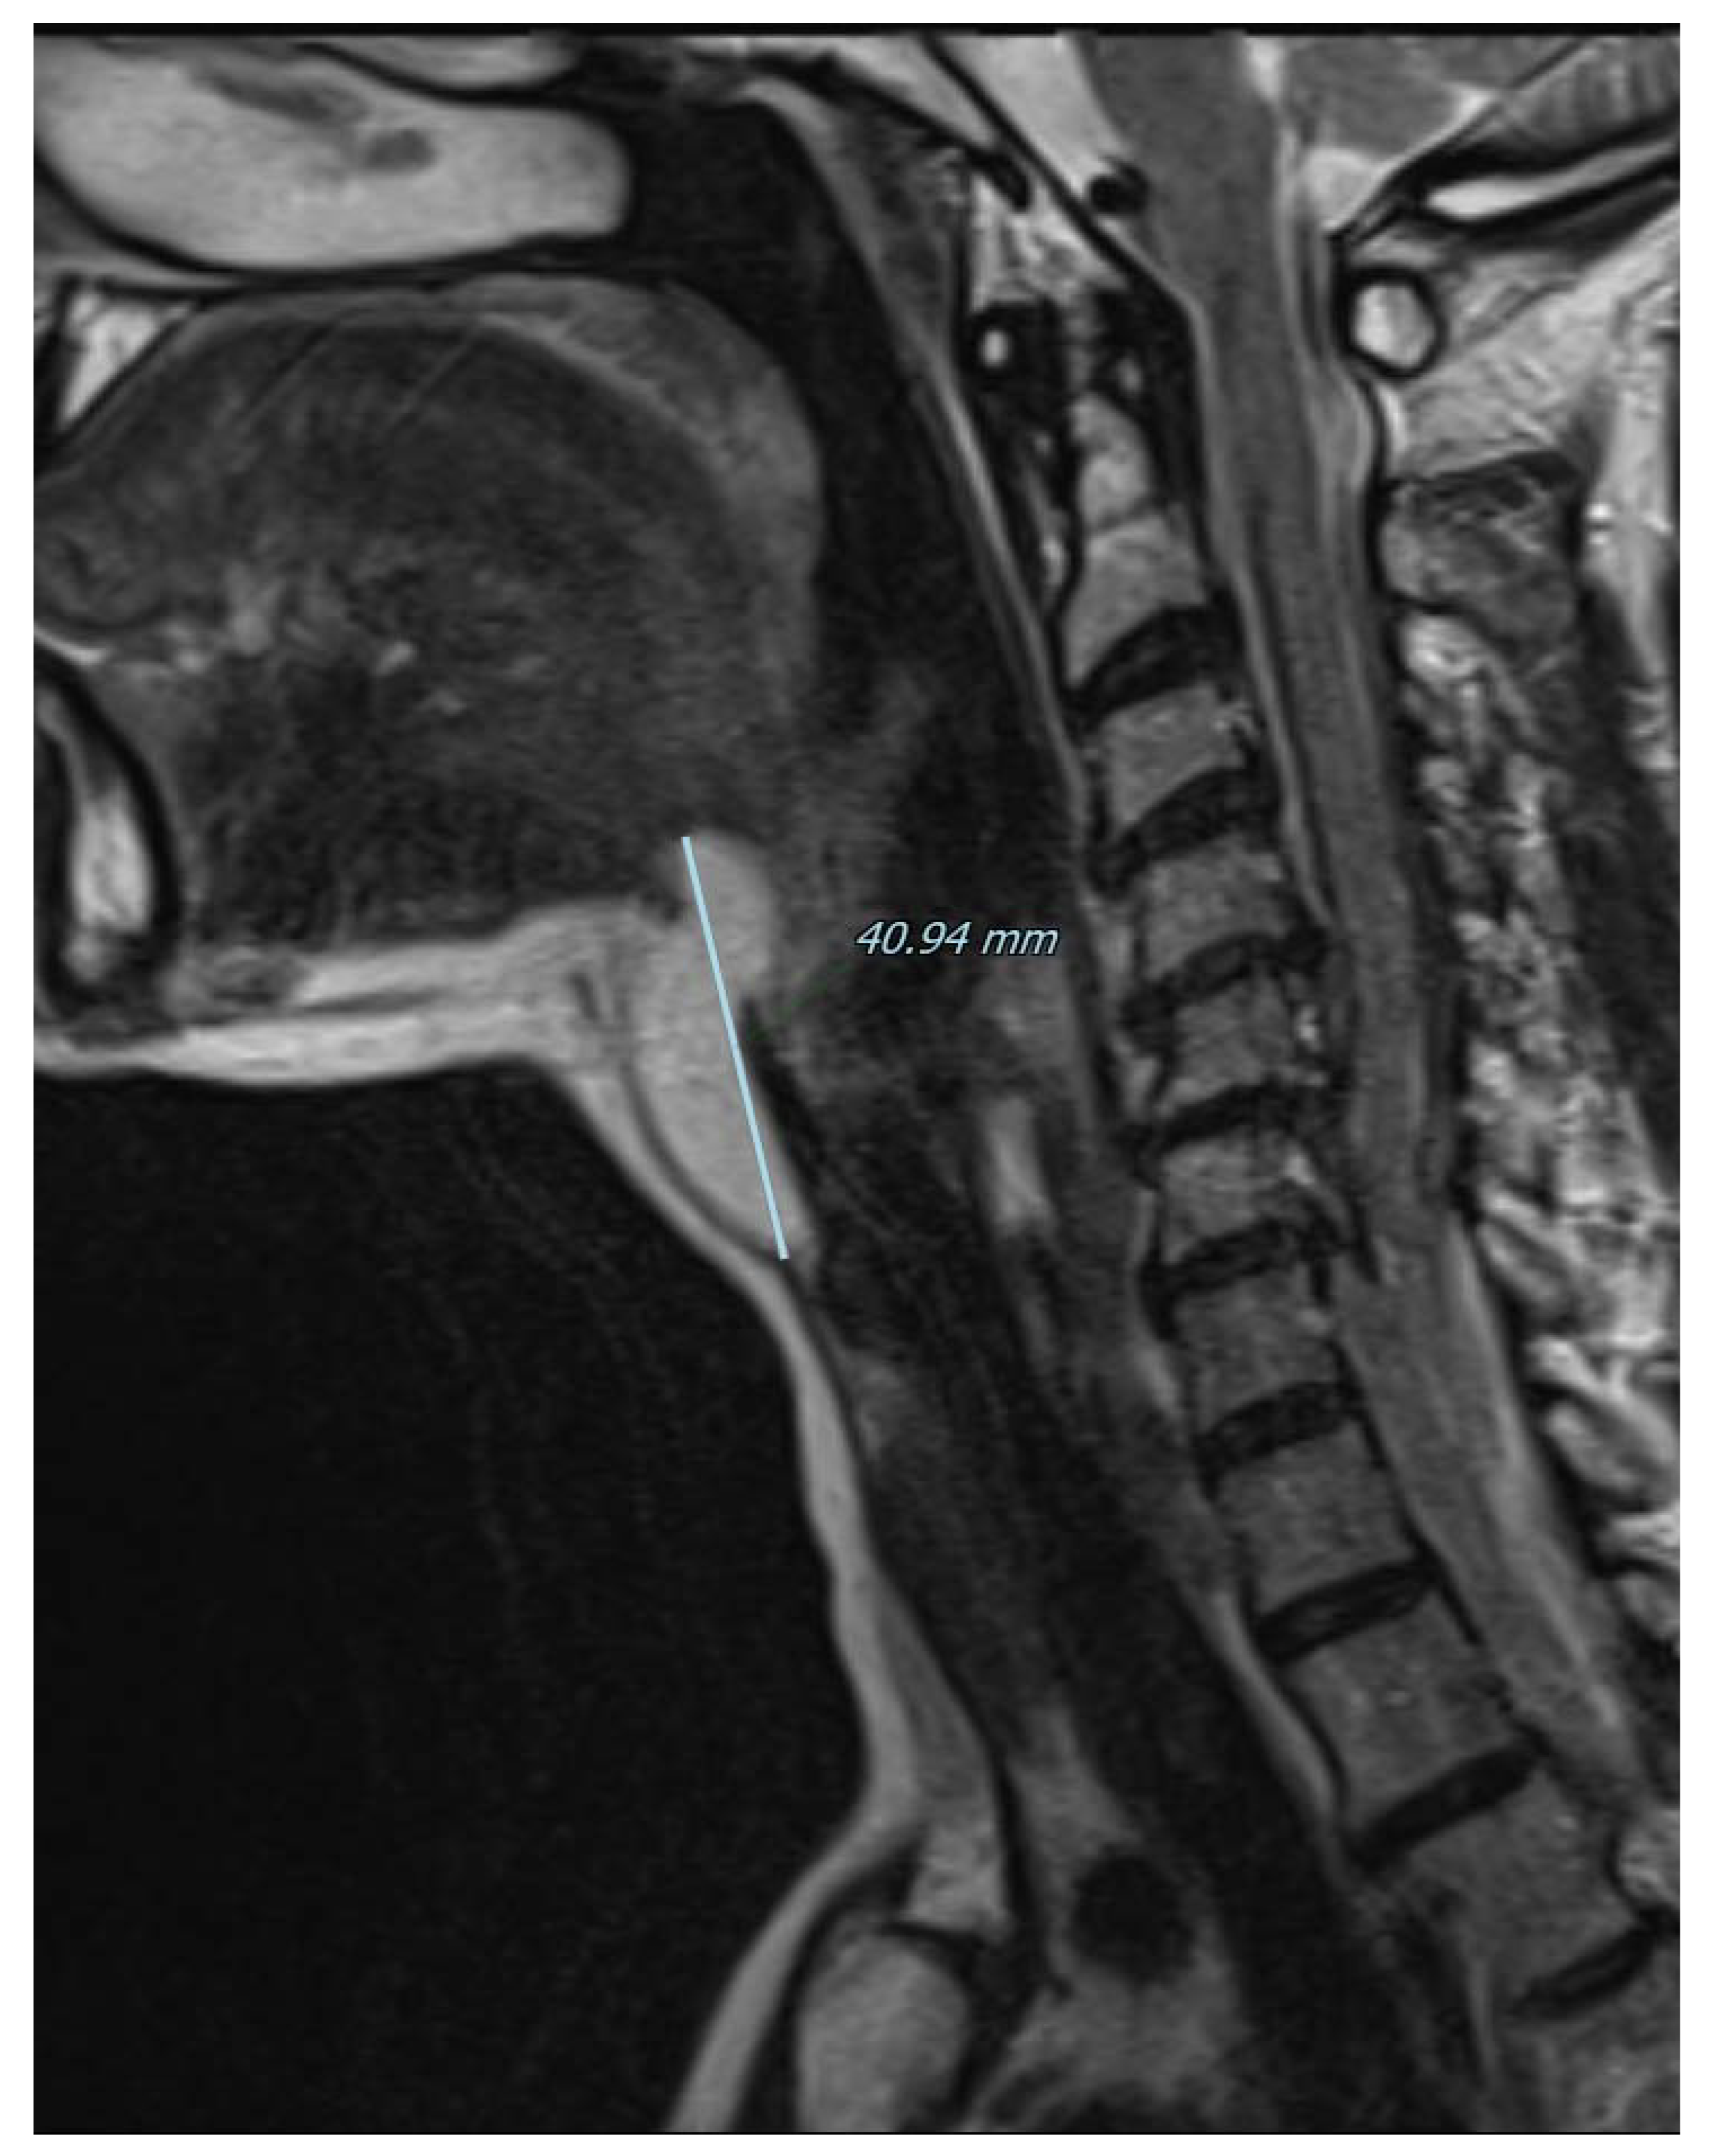

Figure 3.

Magnetic resonance imaging of the neck on a coronal plane, T2-weighted, showing the craniocaudal extension of the mass from the base of the tongue to the anterior neck region. Picture was highly suggestive of lipoma, therefore fine needle aspiration was not performed and the patient was referred for surgical excision under general anesthesia. A subperiosteal dissection was performed in the posterior surface of the hyoid bone that was not transected and the mass was isolated just below the hyoepiglottic ligament and without entering the pharynx. The patient was discharged without any pain or complication on the first postoperative day.